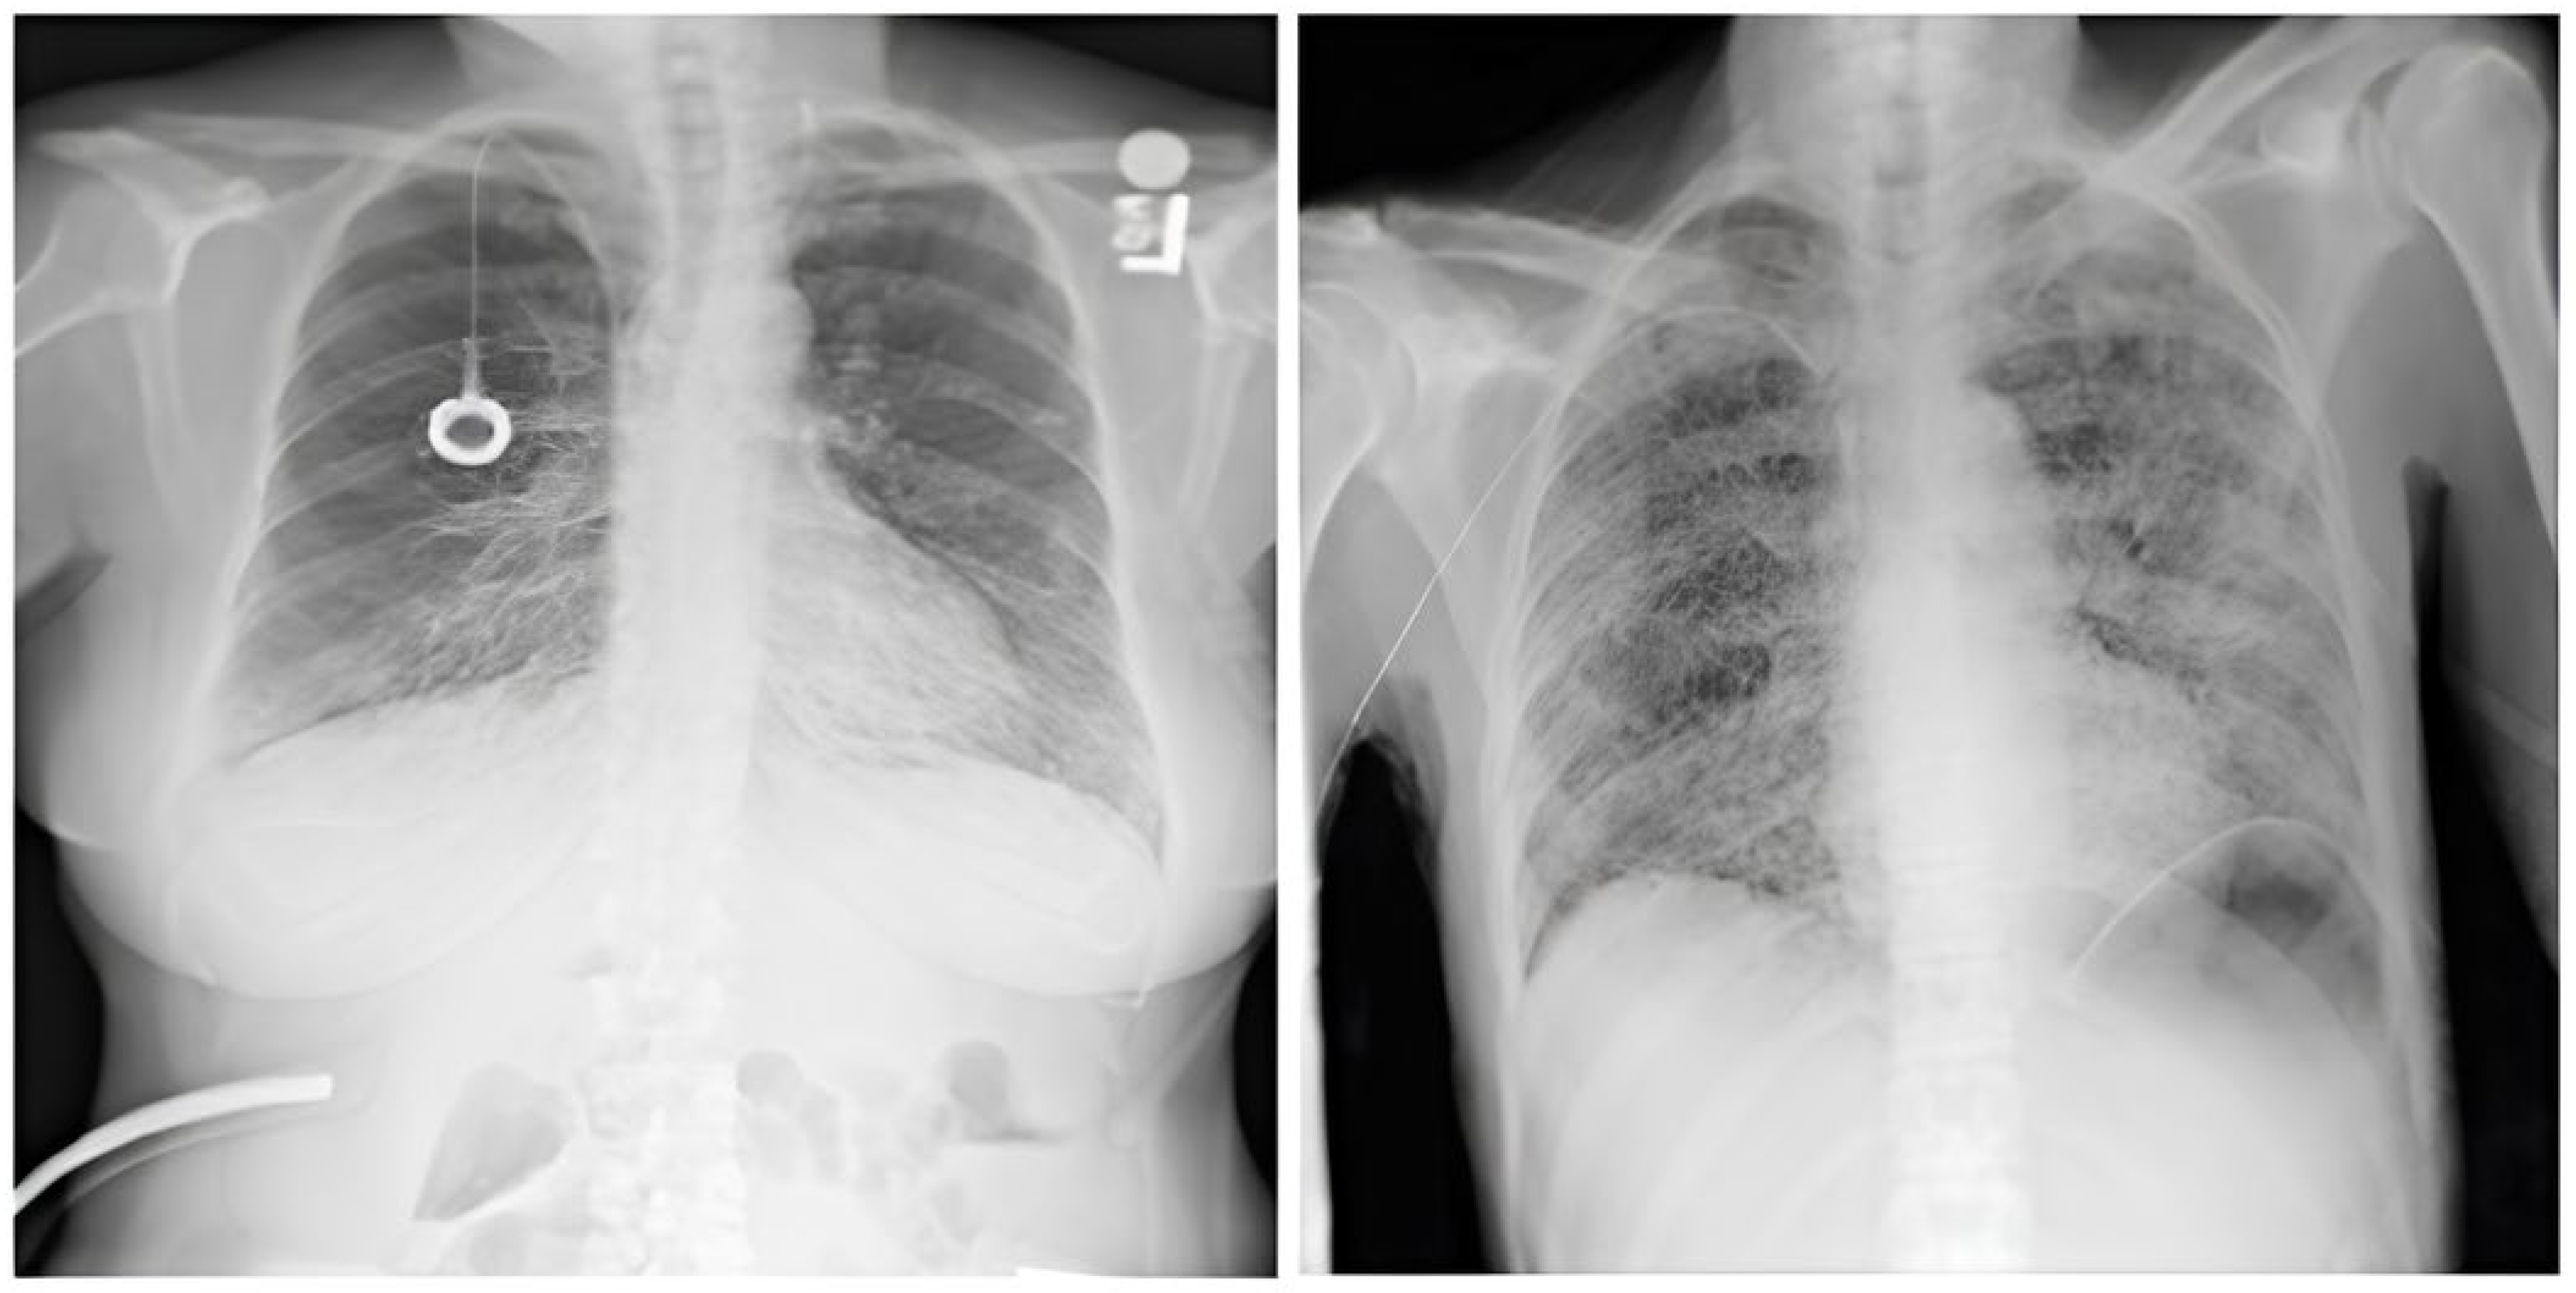

This is an extensive and meticulously curated collection comprising 224,316 chest radiographs obtained from 65,240 patients who underwent radiographic examinations at Stanford Health Care facilities over a substantial timeframe spanning from October 2002 to July 2017 [24,25]. The samples from the CheXpert dataset are shown in Figure 4. These examinations were performed across a diverse range of settings, including inpatient and outpatient centers, ensuring the inclusion of a broad spectrum of clinical scenarios and patient demographics. Each radiograph in this dataset has been labeled for 14 distinct, standard chest radiographic observations, aligning with established clinical guidelines and fostering consistency in labeling across the dataset.

Figure 4.

CheXpert dataset samples [24].

3.1.3. CXR VinDr Dataset

This was developed to provide the research community with a large-scale, high-quality collection of CXR images annotated with detailed and reliable labels [26]. The samples from the CXR VinDr dataset are shown in Figure 5. This dataset was constructed using over 100,000 raw images in DICOM format, which were retrospectively collected from two of Vietnam’s largest and most prominent hospitals: Hospital 108 and Hanoi Medical University Hospital [27]. These facilities contributed to the dataset’s diversity and representativeness by including many cases and patient demographics.

Figure 5.

VinDr-CXR Dataset samples [26].